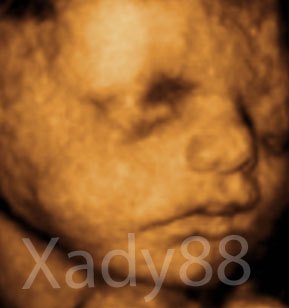

Her er mor og fars lille prinsesse

De to første er fra MD, hvor jeg var 20+